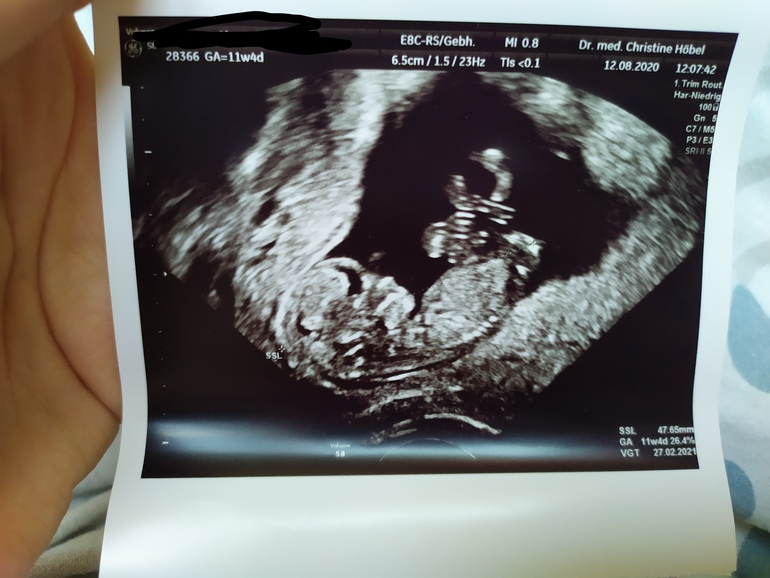

Первый скрининг - done✔️

Пол малышаДобрый день ББ)) сегодня я прошла свой первый скрининг,слава Богу вроде всё в порядке, ТТТ! Тут конечно такой скрининг, НЕДОскрининг... Срок 11+4.

Вопрос к вам девочки, кто что скажет по поводу пола малыша? Мне кажется на этих фото половой бугорок не попал "в кадр", но может вдруг кто разглядит🤪 в Германии пол до 14 недель не говорят😔 для меня это в общем-то не особо важно, хотелось бы девочку конечно, но если мальчик тоже не расстроюсь. Вроде🤭 муж зато наоборот хочет пацана. Ну короч стандартная ситуация 🤦😆 мне главное чтоб ребёнок здоровый родился и желательно под счастливой звездой как говорится 🙈😄

Малышок сначала походу дрых, а потом как забацал сальто и перевернулся на другую сторону)) так мило))) думала буду реветь, неее, лежала как мумия в монитор таращилась с покер фэйс😆 а вот когда уже фото дома начала рассматривать так сидела лыбилась как дура🥴😄😍